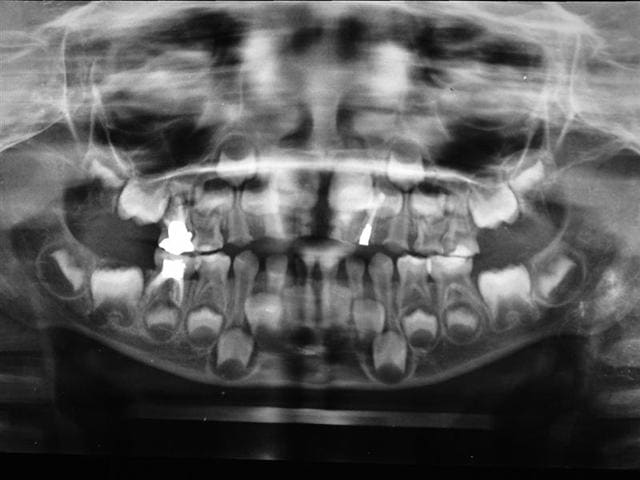

antoine 4 ans1/2

vu en Mars 2007 :traitement 55 -85-51-61

revu en mars 2008 (le printemps?)

prévu:

et commencé

- couronnes pedo(54-64-65-75) sur dts vivantes: trop délabrées pr pouvoir reconstituer correctement en retrouvant une DV correcte mais de la dentine réactionnelle,pas d'infection

-compos sur 53 et 63

-les anterieures je ne sais pas encore...